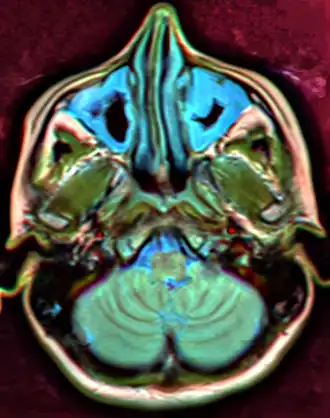

Imaging by either X-ray, CT, or MRI is generally not recommended unless complications develop.[66] Pain caused by sinusitis is sometimes confused for pain caused by pulpitis (toothache) of the maxillary teeth, and vice versa. Classically, the increased pain when tilting the head forwards separates sinusitis from pulpitis.[68]

For sinusitis lasting more than 12 weeks, a CT scan is recommended.[66] On a CT scan, acute sinus secretions have a radiodensity of 10 to 25 Hounsfield units (HU). In a more chronic state, they become more viscous, with a radiodensity of 30 to 60 HU.[69]